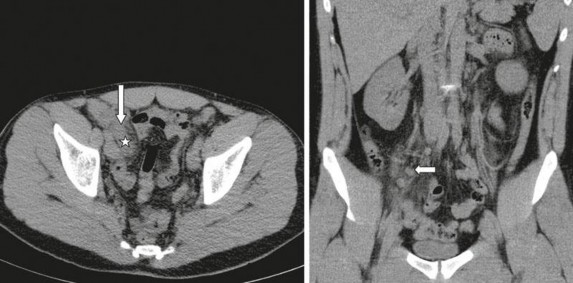

Hình 1.5: CLVT không cản quang ở bệnh nhân VRTC

(Dấu sao). Hình ảnh dày thành (mũi tên) và biến đổi các mô xung quanh trên mặt cắt ngang. Hình ảnh hạch viêm ở hố chậu phải trên mặt cắt dọc [35].